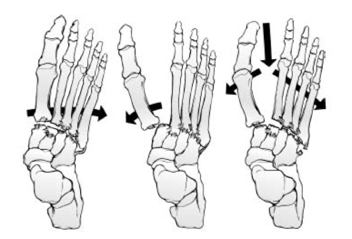

Clasif. Quenu y Kuss: para lesiones de articulacion tarsometatarsianas (Lisfranc), describe la direccion de la inestabilidad:

- Homolateral: los 5 radios en la misma direccion

- Aislada: uno o dos radios desplazados

- Divergentes: los radios estan desplazados en direcciones diferentes